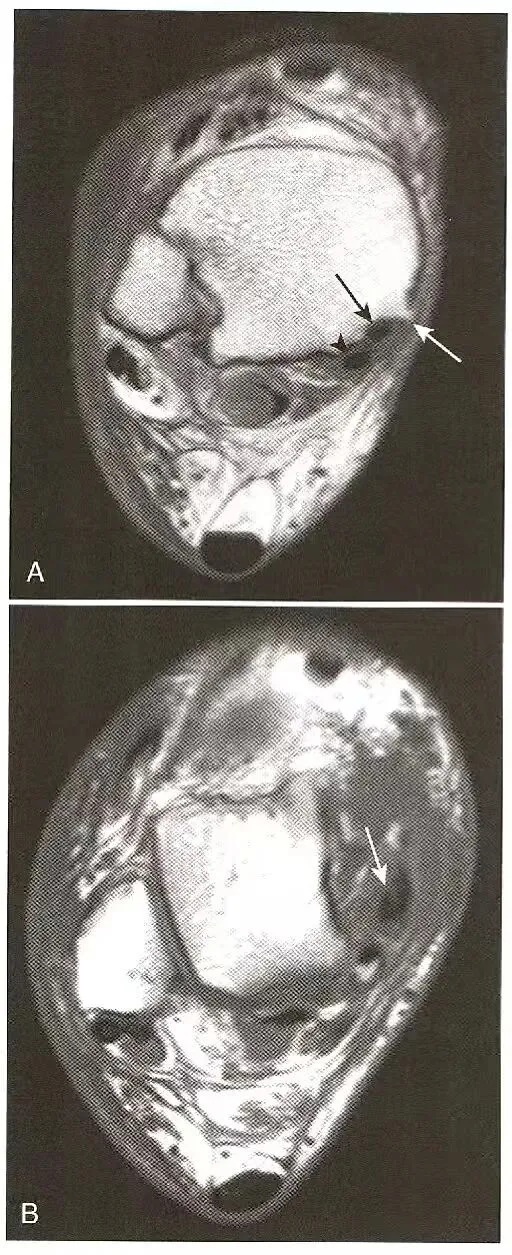

肌腱部分撕裂—纵向分裂:  A,胫后肌(黑色箭号)的大小与相邻的趾长屈肌腱(箭头)相同,表明胫后肌部分撕裂;B,胫后肌腱内裂隙,沿着肌腱的长轴延伸,代表纵向撕裂。